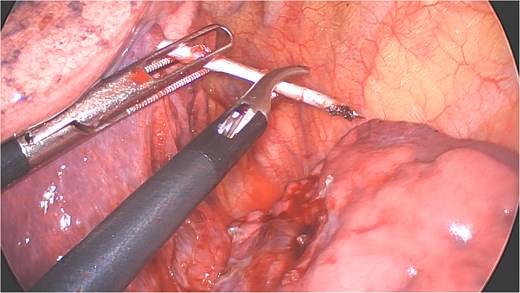

Under general anesthesia with a left double-lumen intubation a left thoracoscopy (VATS) was done using one 11 mm trocar and 2 trocars of 5 mm and a 30° 5 mm camera. We saw a pleural cavity with dense apical adhesions of the left upper lobe against the inferior border of the clavicle (Fig. 3).

Perioperative views of the migrated K-wire, showing dense apical adhesions of the left upper lobe.

A clear minor pleural effusion and translucent scissural and para-aortic adhesions were visible. The adhesions of the pulmonary apex were released but no abnormality of the parietal pleura nor bone was visible. As the lung then collapsed, the pin became spontaneously visible protruding in the main fissure. As expected, the proximal part was in segment 2 and the distal half inside the apical segment of the lower lobe (S6) but it did not protrude outside of the parenchyma on either side (Fig. 4). The K-wire was easily removed by gently pushing back the parenchyma towards both extremities (Fig. 5). The pin seemed to be surrounded by a fine membrane that was coagulated at the visceral pleural entry point.